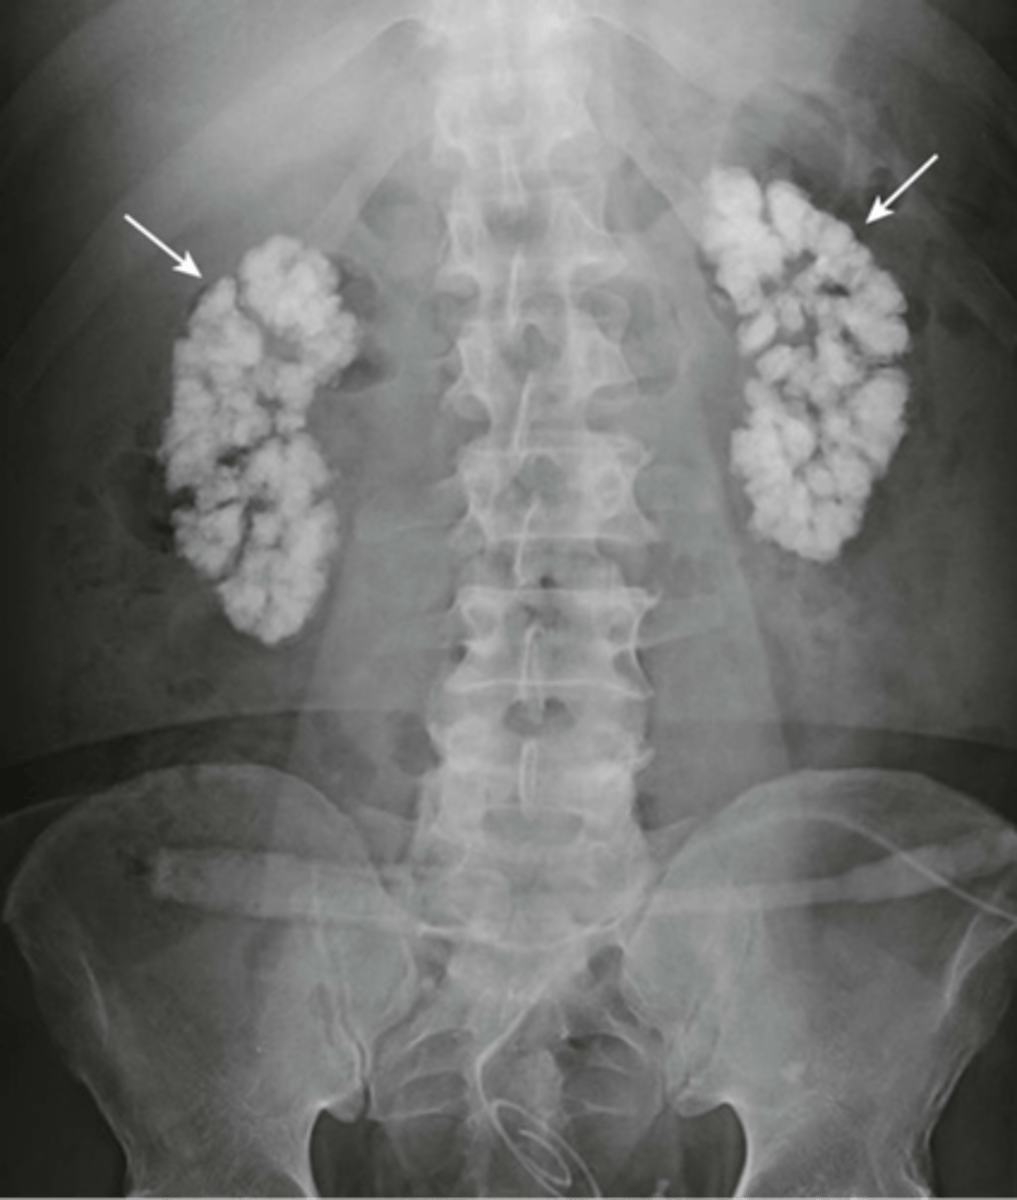

Normal colonic distension (barium enema study)

shows large bowel on barium swallow with fallow through